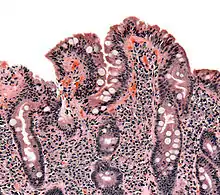

![]() | |

| The ileocecal valve prevents reflux of bacteria from the colon into the small bowel. Resection of the valve can lead to bacterial overgrowth. | |

Finally, abnormal connections between the bacteria-rich colon and the small bowel can increase the bacterial load in the small bowel. Patients with Crohn's disease or other diseases of the ileum may require surgery that removes the ileocecal valve connecting the small and large bowel; this leads to an increased reflux of bacteria into the small bowel. After bariatric surgery for obesity, connections between the stomach and the ileum can be formed, which may increase bacterial load in the small bowel.[26]